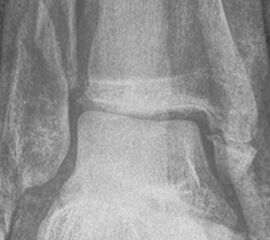

Luxationsfrakturen (Abbildung 7) sollten unter i.v.-Analgesie so schnell wie möglich reponiert werden, um Haut- und Weichteilschäden, Störungen der Durchblutung und Sensibilität, sowie den durch die Fehlstellung bedingten Druck auf den Knorpel zu verringern. Anschließend erfolgt die Ruhigstellung in einem gespaltenen Unterschenkelgips. Offene Frakturen, geschlossene Frakturen mit kritischen Weichteilverhältnissen, sowie hochgradig instabile Frakturen, die sich unter entsprechender Analgesie nicht zufriedenstellend reponieren bzw. retinieren lassen, stellen eine Notfallindikation dar. In diesen Fällen sollte die Anlage eines Fixateur externe erfolgen (Abbildung 8). Die definitive Frakturversorgung erfolgt zweizeitig nach entsprechender Konsolidierung der Weichteile. Eine Kompartment-Spaltung ist bei OSG-Frakturen nur sehr selten erforderlich.